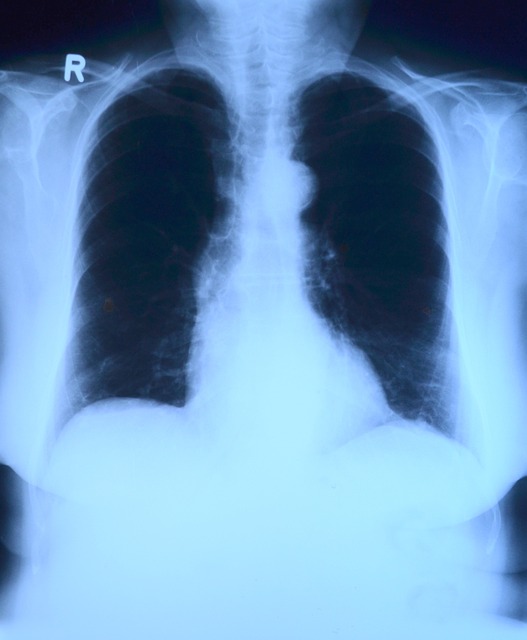

- 영상 검사

- 흉부 X-ray: 폐렴의 범위와 위치를 확인합니다.